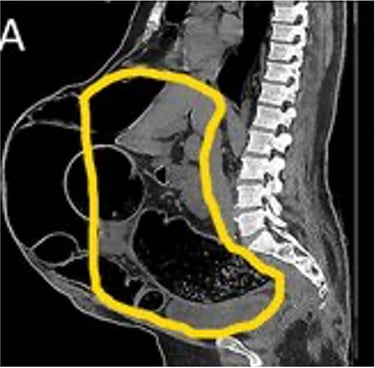

Realizamos una Tomografía Axial Computarizada con reconstrucción en 3D de la Pared Abdominal y de la hernia, cuando corroboramos que todo está listo, el siguiente paso es elegir el tipo de malla quirúrgica a colocar en la cirugía.